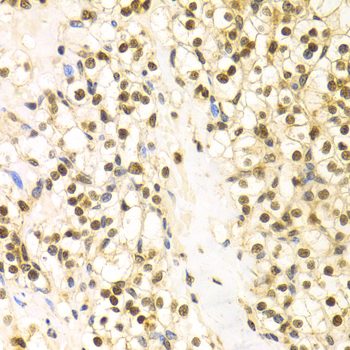

Immunohistochemistry of paraffin-embedded human kidney cancer using BAG1 antibody at dilution of 1:100 (x400 lens).